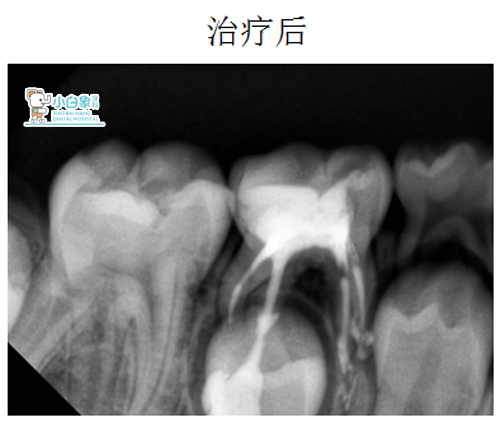

X线片:85低密度影像达髓角

治疗方案:85根管治疗

治疗:85去腐露髓,封慢失一周。复诊开髓揭顶,拔髓,清理根管,冲洗,隔湿干燥,根管内置Vt,磷酸锌垫底,Z250充填。

QQ截图20181220151738